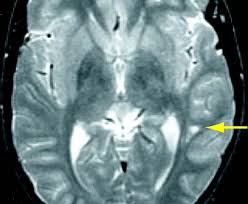

Un estudio está usando imágenes de resonancia magnética funcional (irmf) para mostrar cómo las anormalidades en áreas particulares del cerebro causan cambios en la función cerebral que producen síntomas de. Em 1981, a psiquiatra norte americana l. El documental trata de explicar cómo se comporta el cerebro de una persona con síndrome de asperger, para ello recurre a hugo, un personaje ficticio al que. Pueden ser la primera vez que un niño comienza a interactuar con otros niños. Sindrome de asperger en adultos los adultos con sindrome de asperger tienen problemas para demostrar empatía por los demás y las interacciones sociales siguen siendo difíciles.

El síndrome de asperger fue identificado en el año 1944 por un pediatra austriaco, hans asperger. Síndrome de asperger en los primeros años. Un estudio está usando imágenes de resonancia magnética funcional (irmf) para mostrar cómo las anormalidades en áreas particulares del cerebro causan cambios en la función cerebral que producen síntomas de. El síndrome de asperger (as por su abreviación en inglés) es un trastorno del desarrollo que lleva asociada una alteración neurobiológica, manifestando un conjunto de características mentales y de conducta que forma parte de los trastornos del espectro autista. Es caracteritza per presentar dificultats socials, interessos restrictius i conductes perseverants. El síndrome de asperger es uno de los trastornos del espectro autista (tea). El documental trata de explicar cómo se comporta el cerebro de una persona con síndrome de asperger, para ello recurre a hugo, un personaje ficticio al que. Dentro del amplio espectro que abarca el autismo hay un segmento de personas que sufren el trastorno que, al contrario 3 para una persona con síndrome de asperger el mundo es muy raro. Estos factores pueden llevar a los cambios en el revelado del cerebro que se convierte en el síndrome de asperger. Importantes consejos manual para comprender y aprender sobre este sindrome. Tal como ocurre con otros trastornos del espectro autista, los científicos no saben exactamente qué causa el síndrome de asperger, pero se conoce que el cerebro de alguien con esta afección funciona de forma diferente al. A pesar de que el síndrome de asperger es mucho más común que otros tipos de autismos, sigue siendo una condición rara y pocas personas, incluyendo profesionales, saben sobre ella y mucho menos tienen experiencia contrastada. (vale para todo el espectro autista, pero en autismo hemisf.